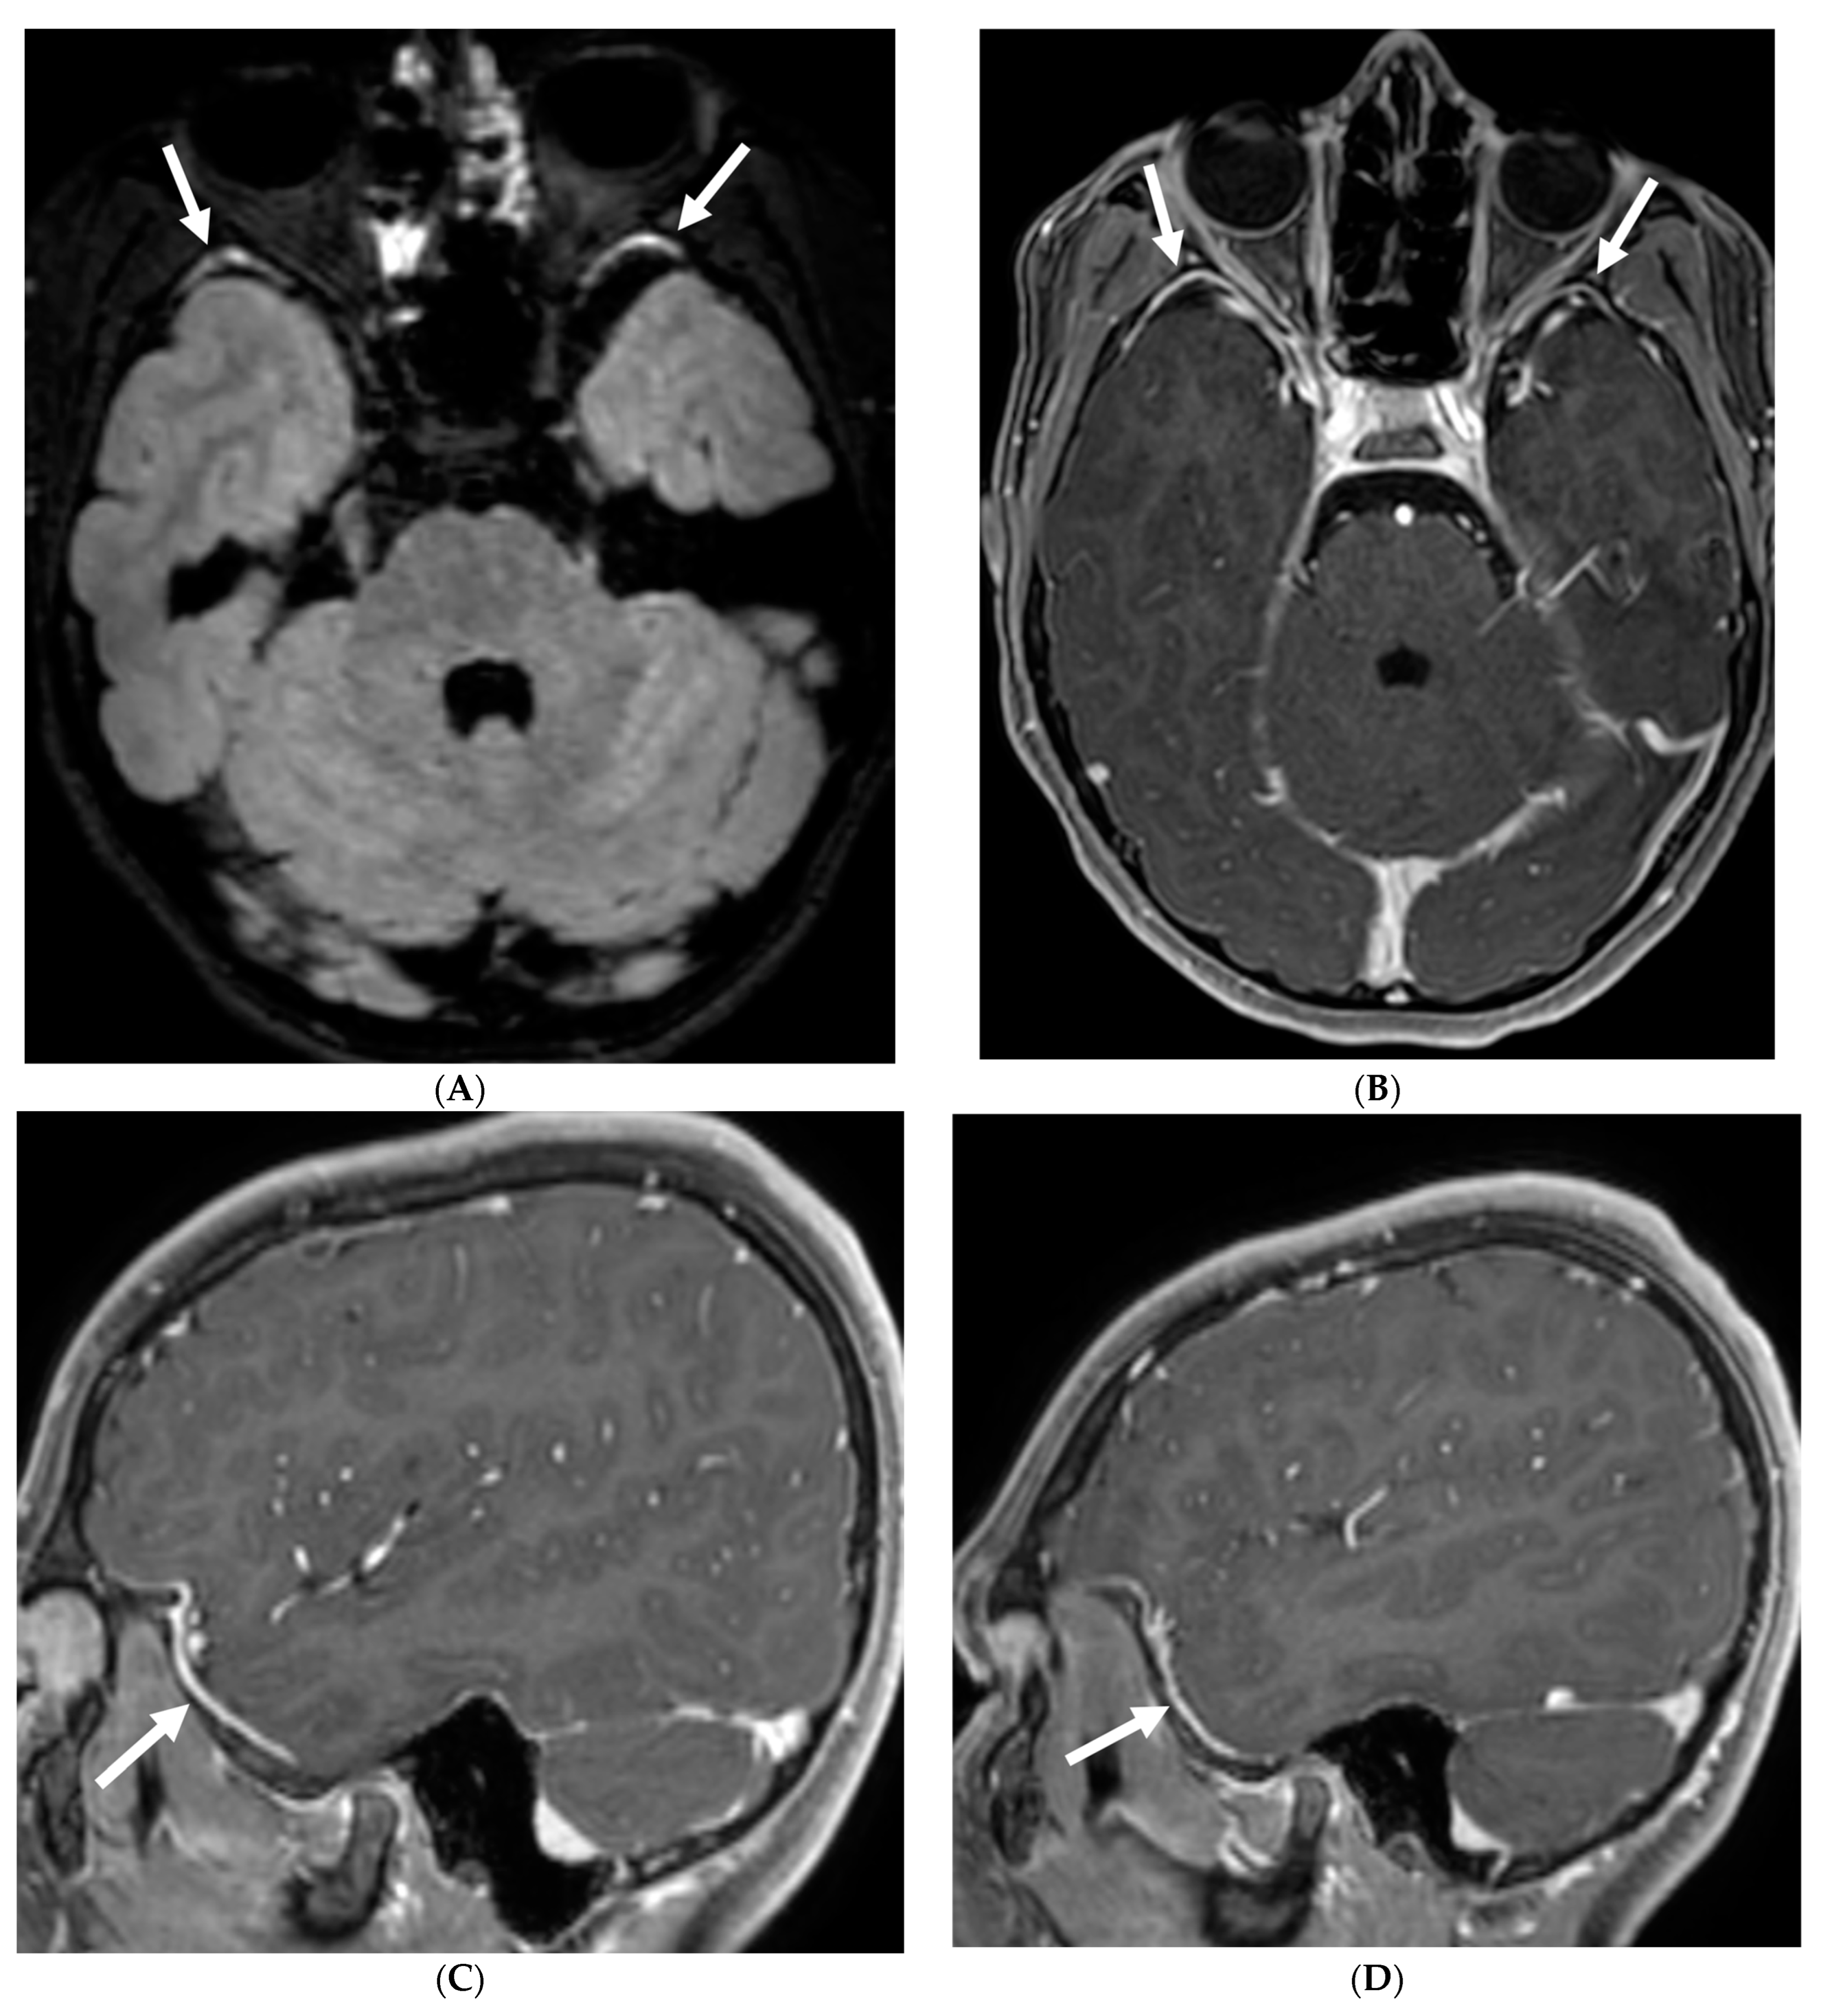

Several viruses, such as enterovirus, herpes simplex virus (HSV)-1&2, mumps, varicella, and arbovirus, can infect children, out of which enterovirus is the most common. These organisms have variable LME, ranging from none to diffuse sulcal LME, best demonstrated on post contrast FLAIR over T1 images [97]. HSV is associated with poor prognosis due to associated parenchymal involvement. HSV-1 commonly causes oral herpes in contrast to HSV-2 which typically causes genital herpes in adults. An active/remote HSV 2 infection in the mother increases the risk of neonatal transmission if delivered vaginally.

HSV 2 typically causes diffuse cortical involvement with diffusion restriction, loss of gray white matter differentiation and basal ganglia involvement in early stages [98]. HSV 1 typically occurs in older children and adolescents and leads to asymmetric temporal lobe involvement with relative sparing of the basal ganglia (Figure 19).

Figure 19.

17-day-old girl with seizures. Axial T2 (A), axial DWI (B), axial T1 post contrast (C), short TE spectroscopy (D) and coronal T2 (E): There is loss of gray white matter differentiation indicating edema in bilateral frontal lobes (arrows). Extensive ischemic changes involving bilateral frontal, bilateral parietal lobes, bilateral perisylvian regions, bilateral thalami (curved arrows). Extensive LME is identified in the effected regions (dashed arrows). Abnormal elevation of lipid/lactate in both basal ganglia and white matter (open arrows). The above constellation of features are concerning for meningitis/cerebritis. Follow up MRI 5 weeks later demonstrates evolution of extensive ischemic changes into extensive cystic encephalomalacia and gliosis in the supratentorial brain, with ex vacuo enlargement of the ventricular system. CSF analysis: HSV-2.